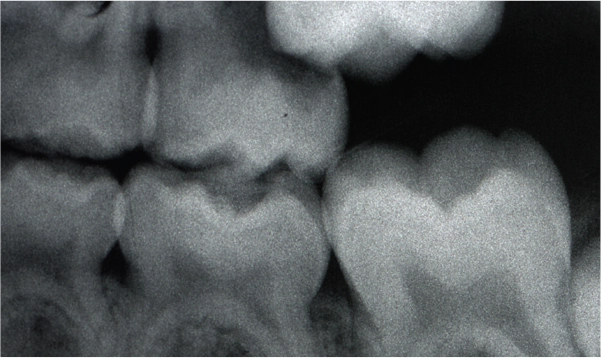

Ectopic Eruption

Ectopically erupting maxillary molar